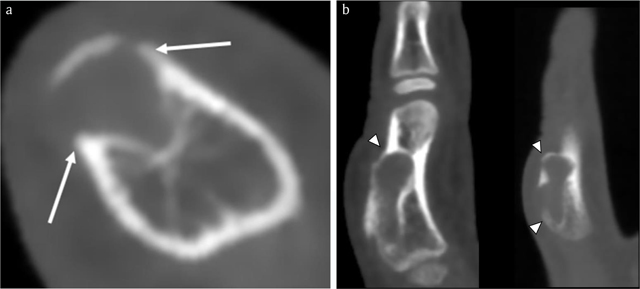

Figure 3

Case 1 – CBCT. Axial image (a). Sagittal reformatted images (2 adjacent slices) (b). Note an expansile radiolucent lesion at the dorsal phalangeal cortex with sclerotic borders (arrows in a). The smaller intramedullary and a larger exophytic components of the lesion are clearly depicted. The cortex is thinned and partially destructed with overhanging edges (arrowheads in b).